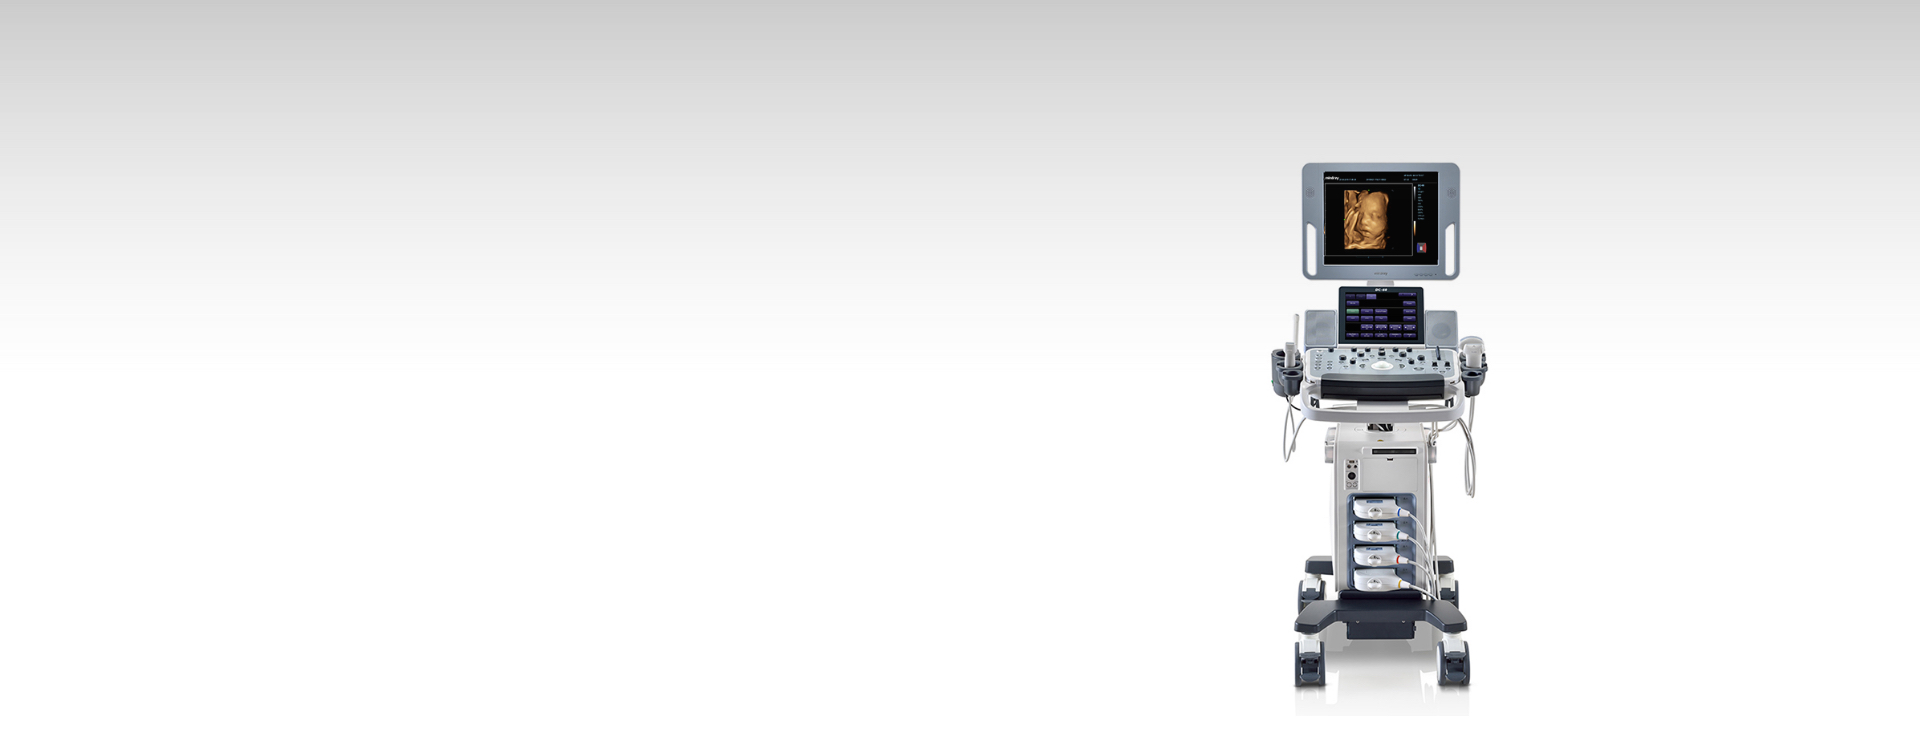

DC-60

Quality Exams at Your Fingertips

Mindray's DC-60, incorporating innovative technologies from advanced ultrasound systems, delivers optimal image quality and a wide range of application capabilities all at an affordable cost. In particular, its unique touch gesture feature is designed to help improve workflow and facilitates ease and confidence of use, enabling you to put patient care first. Automation tools including standardized exam protocols and a number of auto-measurement packages, would help you reduce scan time, and increase everyday efficiency. Mindray understands the reality of tight working spaces, so the DC-60 lightweight system has a small footprint for increased portability and maneuverability. In short, DC-60's capabilities and efficiency make it a practical choice and a good investment for clinicians.